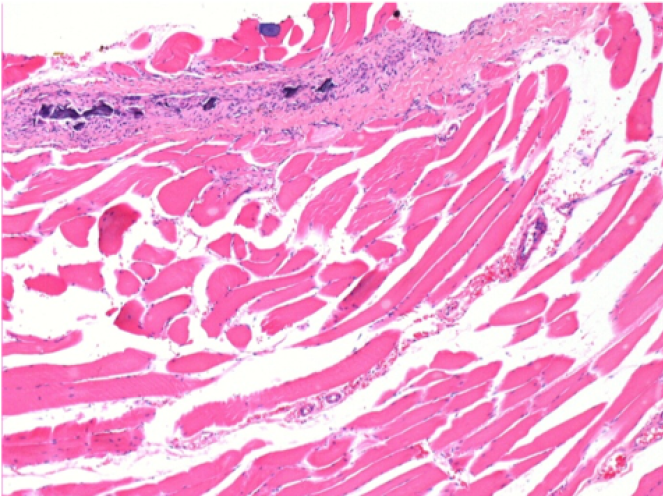

3 months (D90)after Endopeel Injection 0.1ml in the right pretibial muscle.